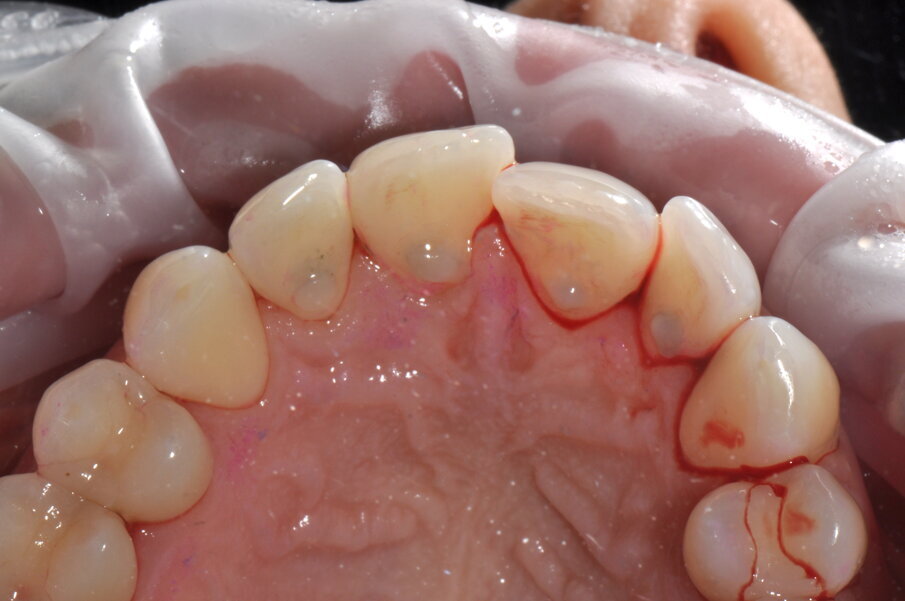

- Applicazione del rilevatore di placca bifasico: permette la distinzione fra i depositi di placca recenti da quelli meno recenti ( 1a-1c);

Figg. 1a-1c - Applicazione del rilevatore di placca che verrà usato come guida durante la terapia, nel versante vestibolare (1a), palatale (1b) e linguale (1c). Si noti lo scarso livello di igiene orale domiciliare e l’assenza di utilizzo dei presidi interdentali.